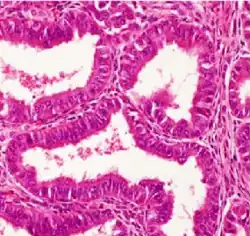

| Surface epithelial-stromal tumor | Serous tumor | 25% | 18.5% | Benign serous tumors of the right ovarian cyst are thinwalled unilocular cysts that are lined by ciliated pseudostratified cuboidal or columnar epithelium.[9] |

|

| Mucinous tumor | 15% | 8.8% | Benign mucinous tumors of the ovary consist of simple, nonstratified columnar epithelium with basally-located hyperchromatic nuclei and resemble gastric foveolar epithelium.[9] |

| |